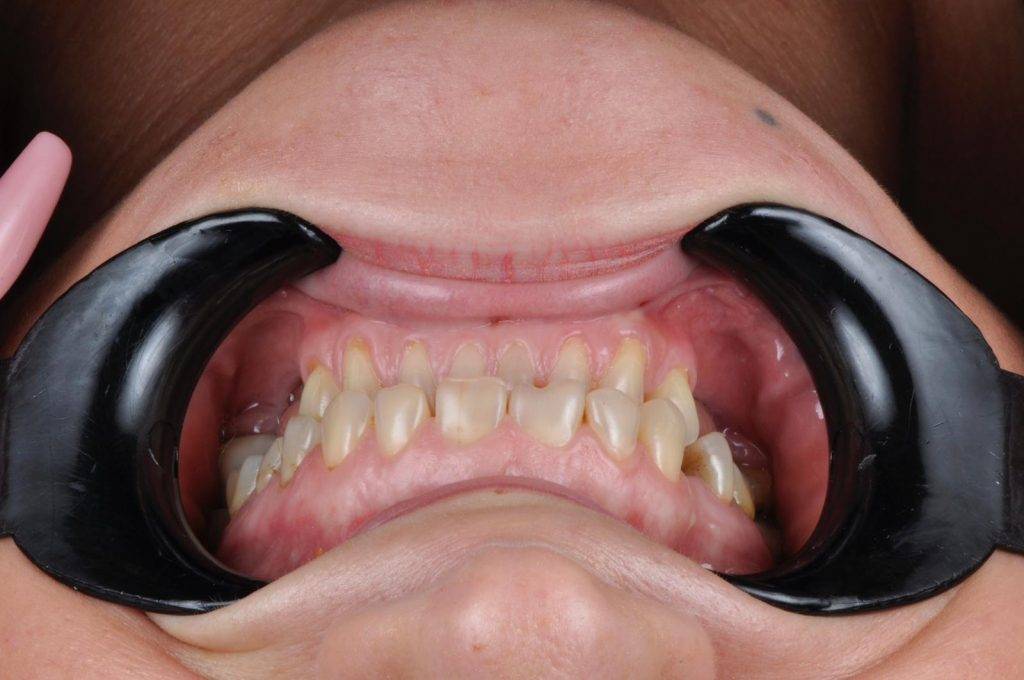

Unsere Galerie

Über 1000+ glücklichen Patienten

Glückliche Kunden Zahnmedizin